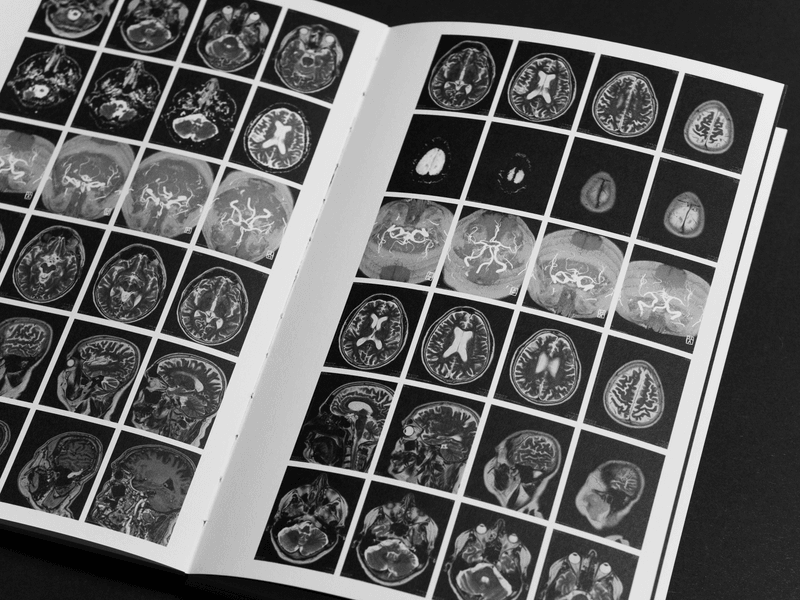

Mein Vater Armin – Schmerzen für immer